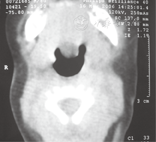

23例LTGDC患儿均行喉部CT扫描(图2、图3),可见舌根后方出现低密度囊性病变,囊壁均匀、边界清,直径10~30 mm,平均直径17 mm,舌根水平气道狭窄,矢状位见囊肿均位于舌骨后上;有8例同时行MRI检查,病变位于舌根后方,MRI示T1WI低信号,T2WI高信号。喉部CT/MRI可以提供病变范围、与周边关系等更多的解剖信息,避免漏诊。特别是MRI检查有助于对喉镜下无法判定囊肿基底部位的LTGDC与会厌囊肿(病变位于会厌谷)进行鉴别(图4)。6例患儿同时行颈部超声检查,仅1例发现病灶,表现为包膜完整、边界清楚的低回声。